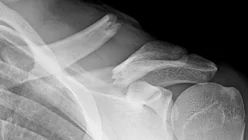

- Sites:

- Lateral thirds,

- Middle thirds, common (why?)

- Medial thirds

Its weakest point. The lateral fragment is depressed by the weight of the arm against trapezius, thus the shoulder droops, it is pulled medially forward by adductor function of pectoralis major causing the bone fragments to override.